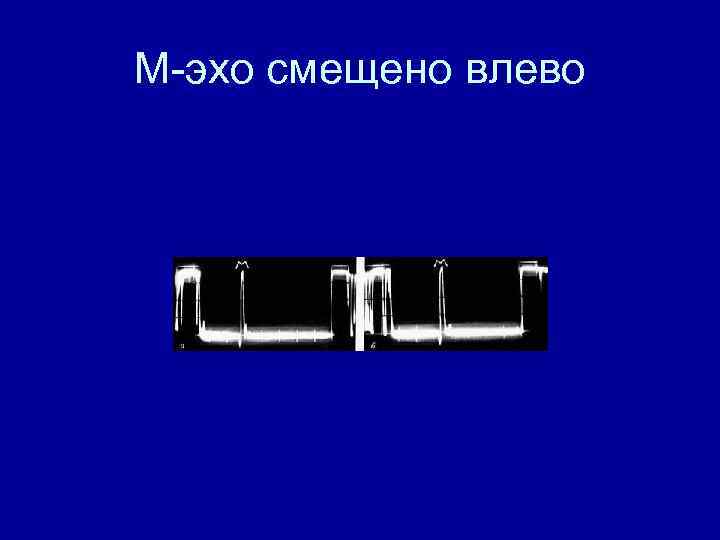

М-эхо смещено влево

М-эхо смещено влево